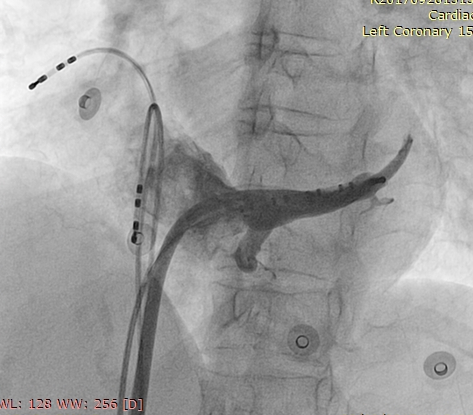

CS venogram

cs_venogram00001.jpg